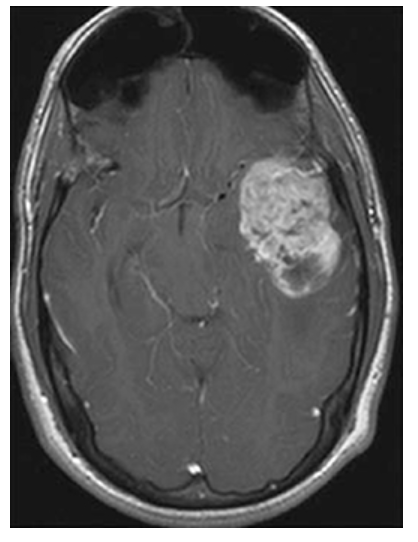

Astrocytoma. Postcontrast axial T1W image shows enhancement of the mass in the left temporal lobe. There is mass effect on the surrounding brain with effacement of the left ambient cistern.